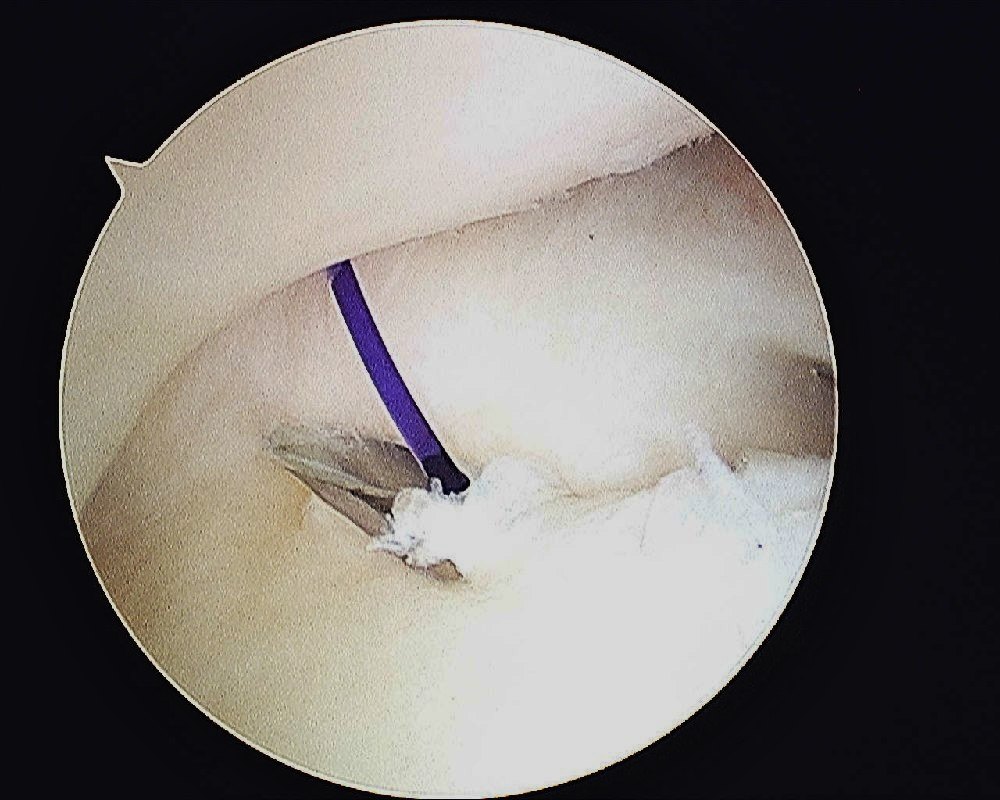

- TFCC Tear – Palmer Type IB

A PDS 3/0 suture is passed into the joint and retrieved through the 4/5 portal using a small arthroscopic grasper